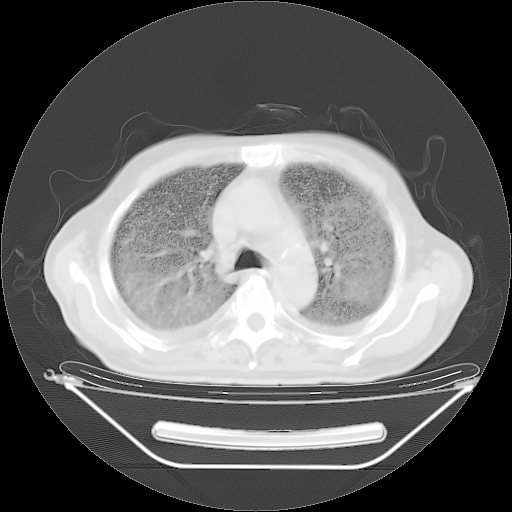

今天复查肺部CT,发现双肺广泛磨玻璃样改变。所以我把3月19日和5月9日相隔50天的肺部CT上传。请大家会诊。

2009年3月19日肺部CT片。

2009年3月19日肺部CT

大致读了系列胸部CT:纵隔窗无明显异常,肺窗:从4、27至今:主要是双肺中下野外带可见毛玻璃样改变,目前处于急性肺泡炎阶段,至于原因考虑1、结替组织或胶原血管性疾病所致?2、恶性疾病如恶组在肺部所致的表现或细支气管肺泡癌?3、药物或其它原因如肺蛋白沉着症所致肺泡炎目前不太可能?总之,明天就去请我院的呼吸科、感染科、血液科和临免专家会诊哈。